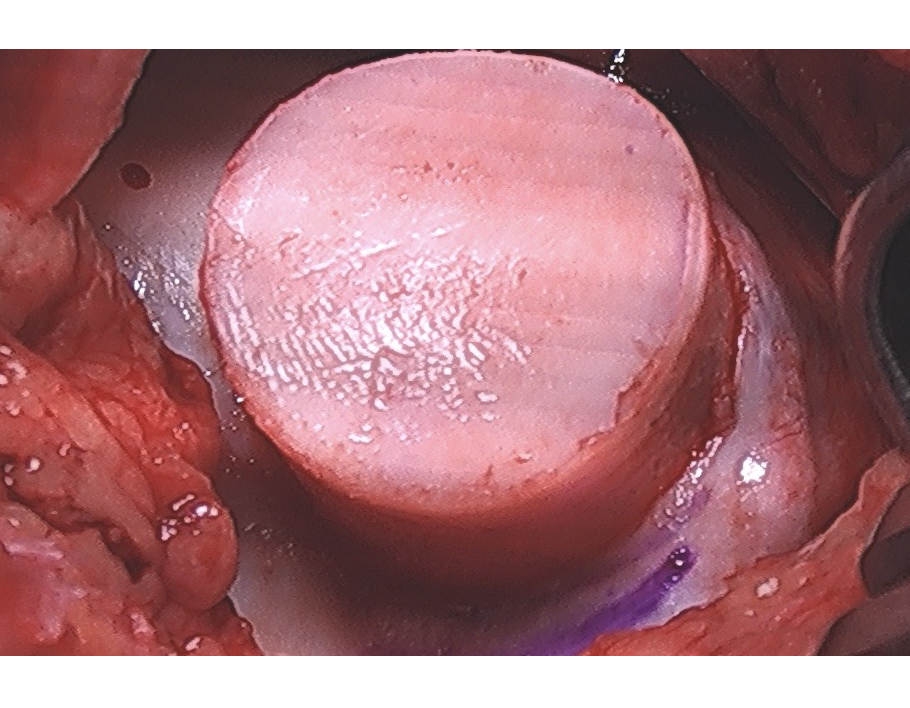

Cored Recipient Trochlear Site

OATs Plug

OATs Implantation

Implanted OATs